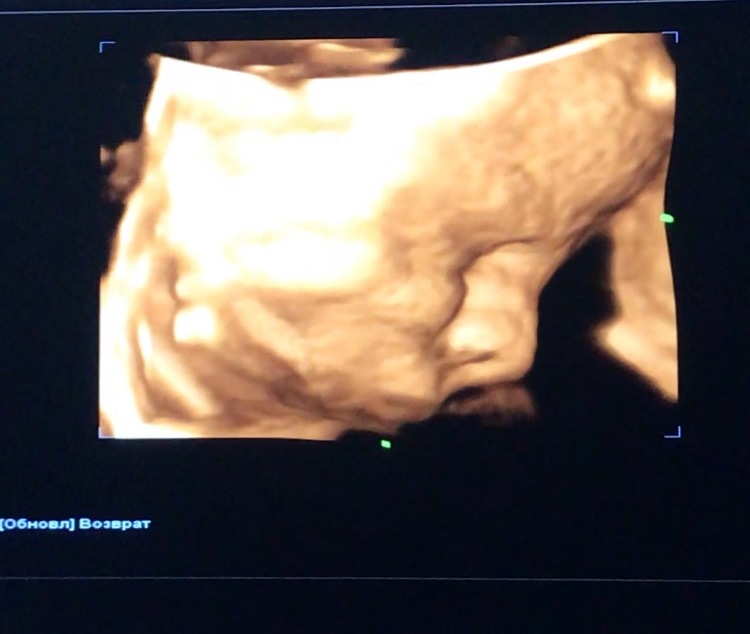

Узи скрининг в 31 неделю

Результаты: УЗИ, КТГ, доплера, скринингаНизкое предлежание плаценты, опережаем в развитии на 2 недели, вес 2 кг, небольшое обвитие вокруг шеи, но все хором кричат ничего страшного. Ходили на 4D узи с дочкой и мужей, оборжались, врач сказал вы бы еще в 40 недель пришли чтобы увидеть в монитор только мочку уха, а так говорит покажу вам на весь экран целое ухо)))

В 4D дочка сказала что ее братик инопланетянин)) А я все увидела и поняла сынуля похож на меня особенно носом и губами))

Выкладываю фото)) Оно смешное)) Кидайте свои фотки с узи)

Вот наш щекастик в 33-34 недели 🙈

Да)) и на верхней и носик и губы похожи)) он ещё во время УЗИ губки немного вперёд сделал и вообще такой кругляха стал, хотя мы с мужем скорее худые🙈🙈🙈 в кого он такой, я не знаю😁😁😁

Божечки какая прелесть ТТТ на вас)) блин какое классное узи, у нас вообще в камеру не смотрел, никак не поймать было только в профиль.